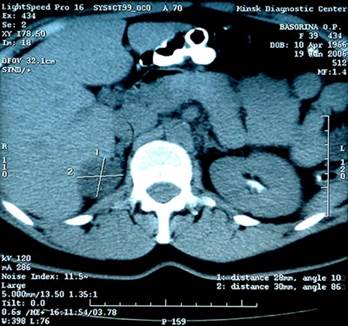

В сроки от 1 года до 3 лет после операции выполнены контрольные УЗ-исследование (14 - 46,7% - пациентам контрольной группы и 30 - 81% - пациентам основной группы) и компьютерная томография (3 - 8,1% - пациентам основной группы). Изменения (объемные образования) выявлены у 5 (13,5%) больных основной группы, но в неоперированном надпочечнике (рис. 1).

Рисунок 1. Компьютерная томограмма пациентки, перенесшей лапароскопическую адреналэктомию левого надпочечника. Определяется объемное образование в области правого надпочечника.